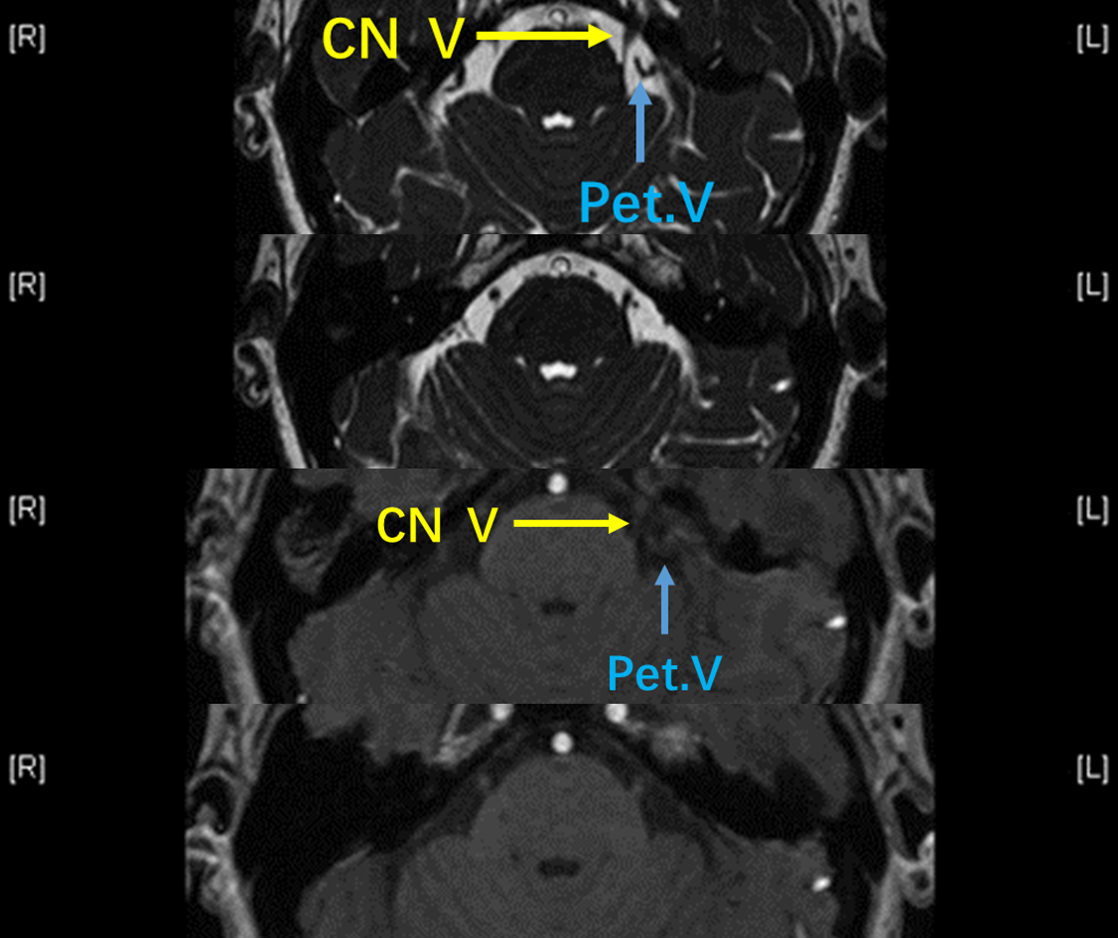

3D-TOF-MRA未见左侧三叉神经周围有可疑动脉血管。

再观察FIESTA序列,可见左侧三叉神经外侧有一根较粗血管与之关系密切,而TOF序列上信号强度(等信号)与动脉不符,考虑静脉压迫。

镜下所见:桥脑三叉静脉(岩静脉属支)于三叉神经外侧压迫(与第三支痛相吻合)。

Tefflon垫绵充分减压,患者术后疼痛立即消失,恢复良好。